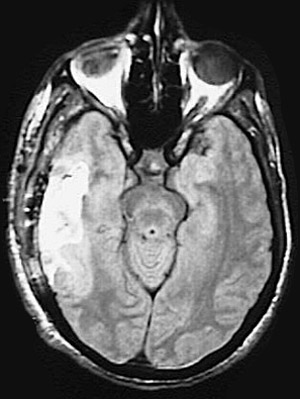

Click on the area of hemorrhage in the MRI scan above:

This axial MRI scan demonstrates a large area of hemorrhage in the right temporal lobe as a consequence of a ruptured vascular malformation.